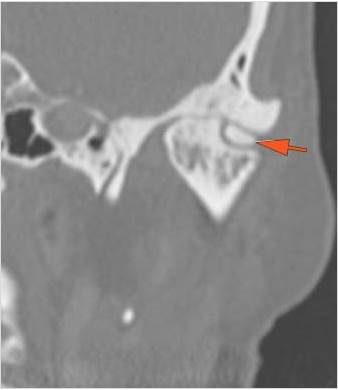

The condylar head and fossa as well as the temporomandibular joint space are fractured and/or dislocated. |

Yes | NA |

There is condylar fracture either within or outside of the joint capsule, or with or without involvement of the articular surface of the condylar head. |

There is evidence of radiodense intra-articular osteochondral fragments. |

No | NA |